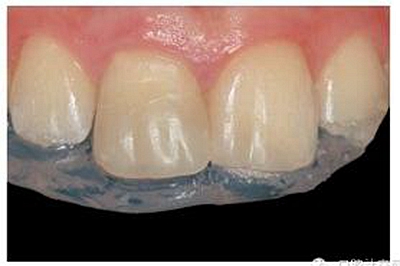

牙本質(zhì)和牙釉質(zhì)經(jīng)過全酸蝕(酸蝕劑)后,涂布粘接劑(Syntac; Ivoclar Vivadent),準備樹脂修復。利用已完成的硅膠導板輔助修復體的腭側(cè)成型(圖13)。牙本質(zhì)核采用不同顏色、不透光的牙本質(zhì)樹脂分層連續(xù)堆積

切端則采用透明樹脂,最后使用釉質(zhì)樹脂(Amaris, VOCO, Cuxhaven, Germany)。21的樹脂修復采用類似的方式。修復初步成型,拋光,恢復干燥牙釉質(zhì)的顏色。攝片顯示樁在根管內(nèi)位置合適(圖15)。最后一次復診精修、拋光充填體,完成治療。